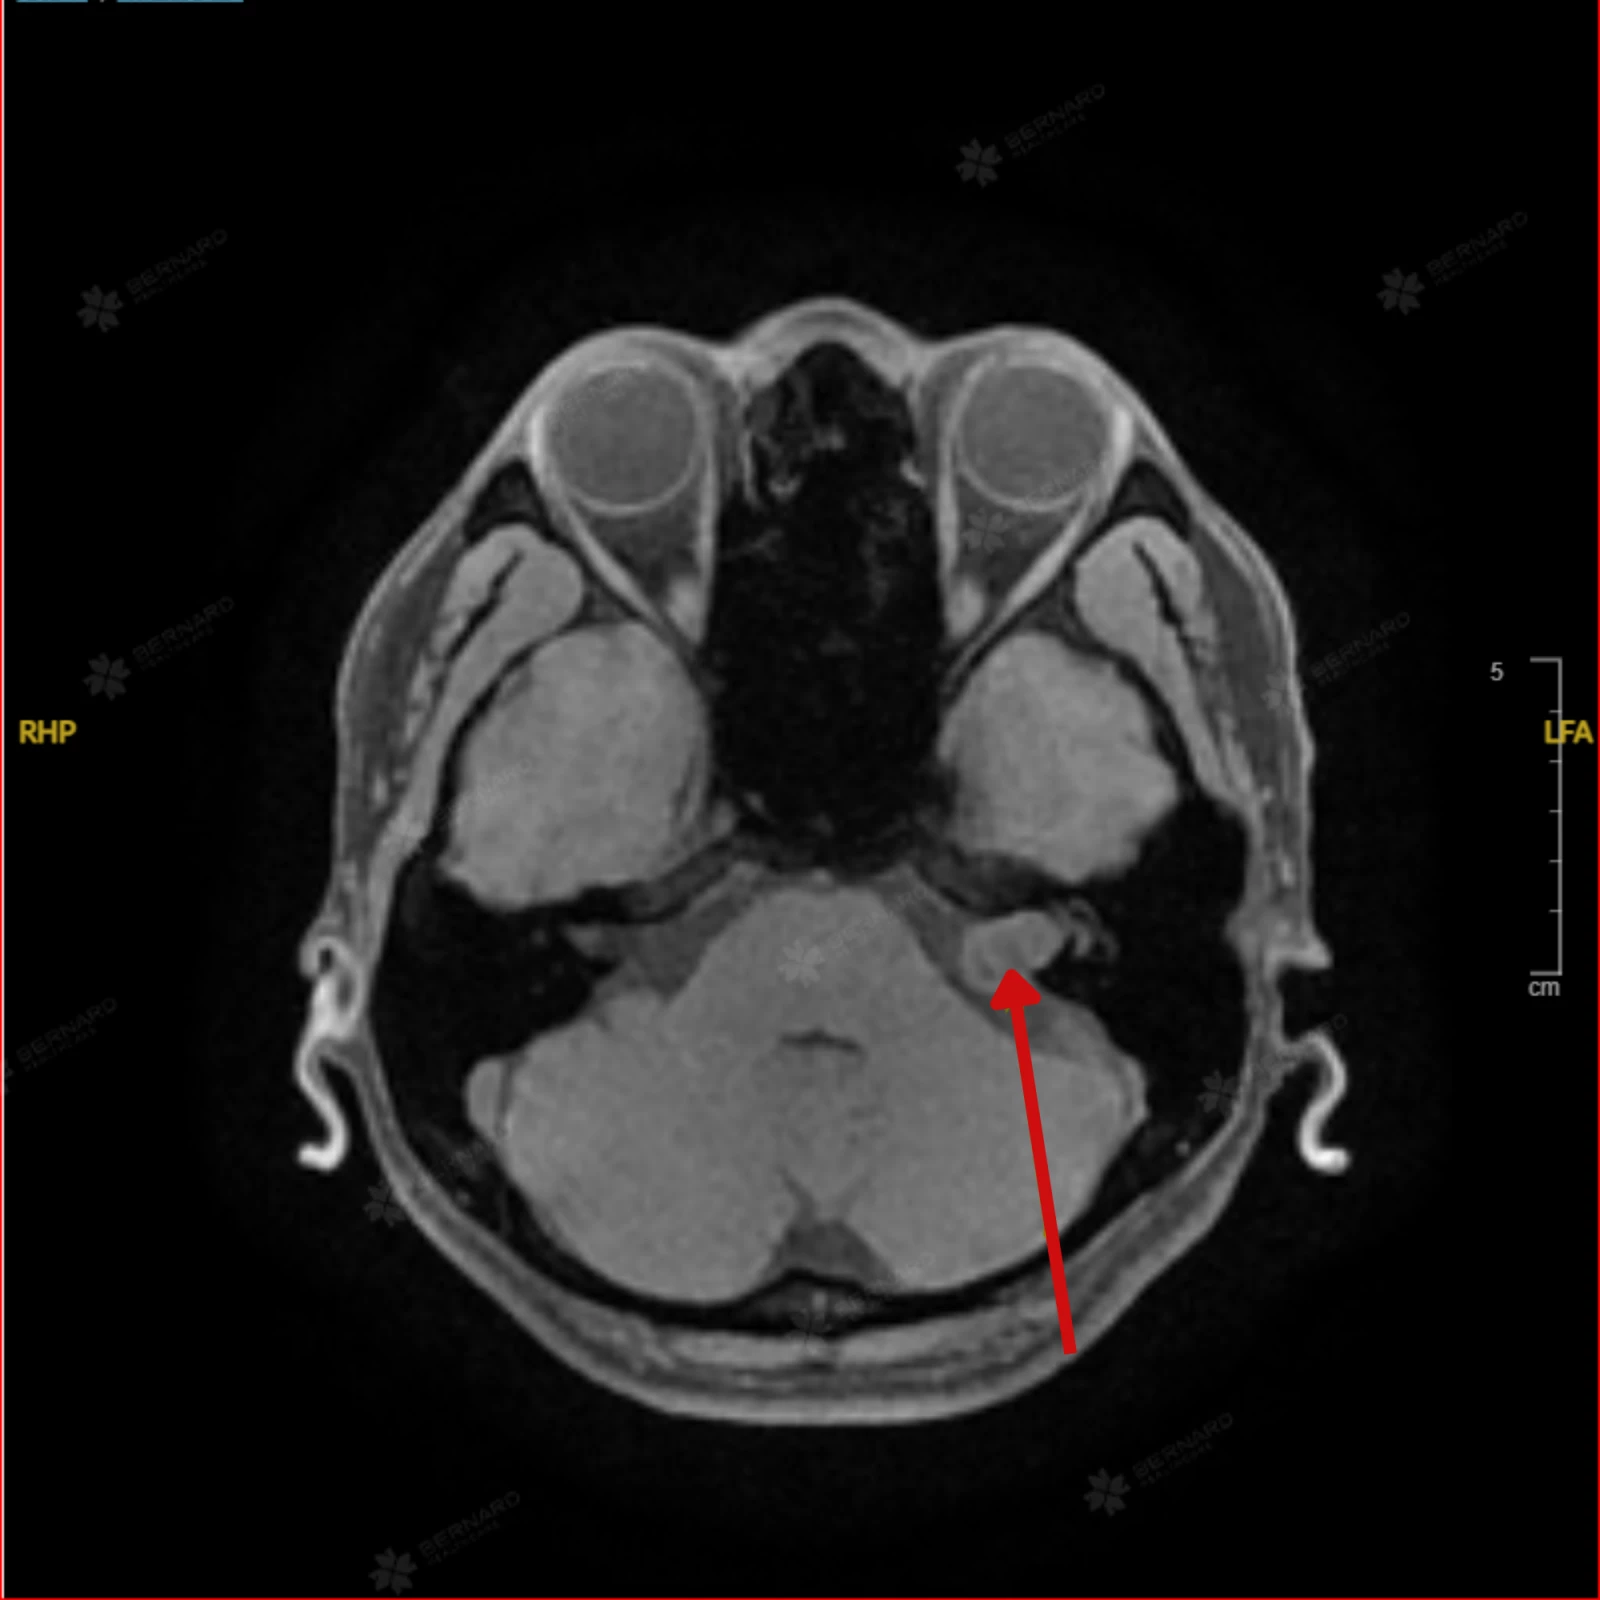

Kết quả MRI não ghi nhận: Tổn thương choán chỗ ngoài trục tại vùng góc cầu tiểu não trái, lan vào ống tai trong trái, kích thước khối u khoảng 10 x 12 x 16 mm. Hình ảnh tổn thương gợi ý u góc cầu tiểu não trái lan vào ống tai trong, nghĩ nhiều đến schwannoma (u bao dây thần kinh).